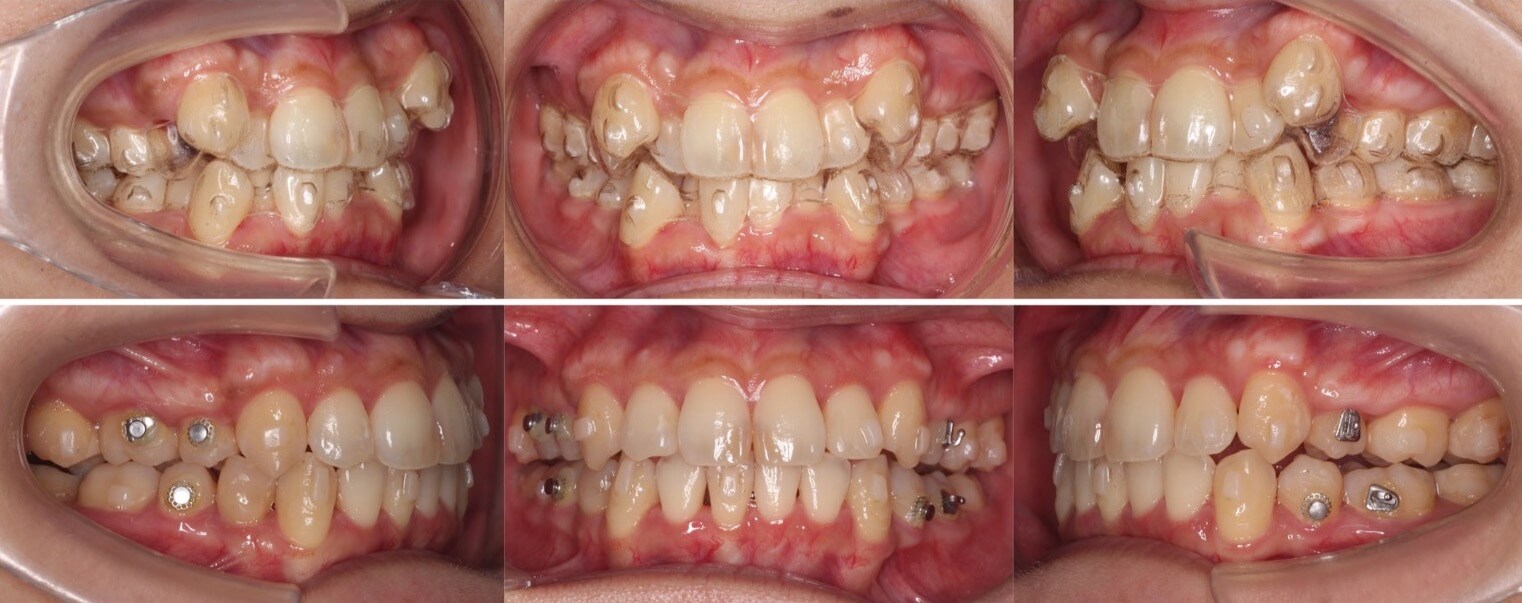

46歳女性・唇側矯正装置・抜歯

<症例概要>

主訴:前歯と口元の突出

年齢・性別:43歳女性

住まい:千葉県佐倉市

症状:叢生・上下顎前歯唇側傾斜

治療方針:上左右5番・下左右4番(計4本)

治療装置:唇側矯正装置

固定装置:ナンスホールディングアーチ

治療期間:3年

リテーナー:下フィックス+上下クリアタイプ

治療費用:968,000(税込)

代表的副作用:痛み・治療後の後戻り・歯根吸収・歯髄壊死・歯肉退縮

▶︎その他の副作用

前歯の突出のため口が閉じづらいことを気にされていて矯正治療を希望された患者さんです。年齢的に抜歯を行うか迷ったのですが、患者さんの主訴を優先して抜歯矯正により前歯を後方移動させました。抜歯部位については、上の歯並びは治療歯である第二小臼歯(5番)を選択しています。その分、治療期間は3年を超えてしまったのですが、理想的な横顔になりました。